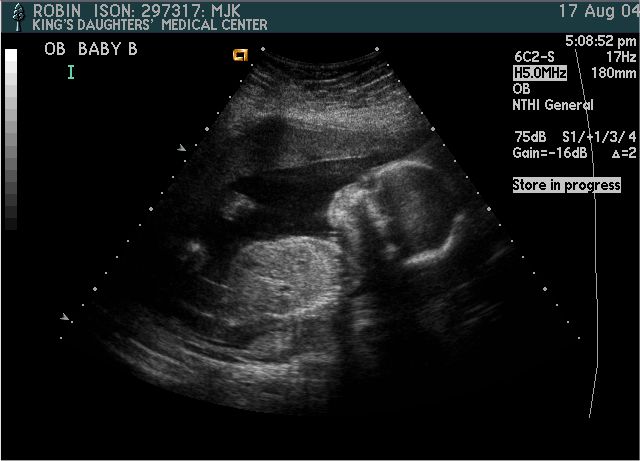

Baby B

Pictures from Ultrasound at 20 weeks.